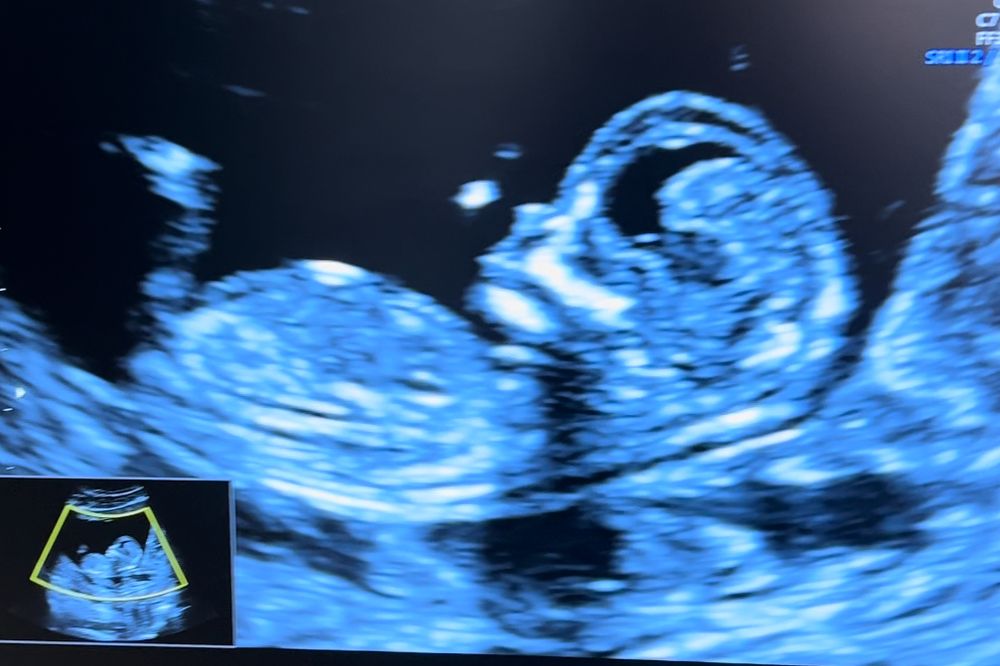

Скрининг 1

Кто в животике живёт (гадаем по фото УЗИ; результаты НИПТ или УЗИ)

Врач сказала, что может предположить пол, но говорить не будет, это ее принцип. А мне конечно интересно) кто разбирается, видно мальчик или девочка?

12 недель 5 дней

По половому бугорку могу предположить пацана. У девочек он другой